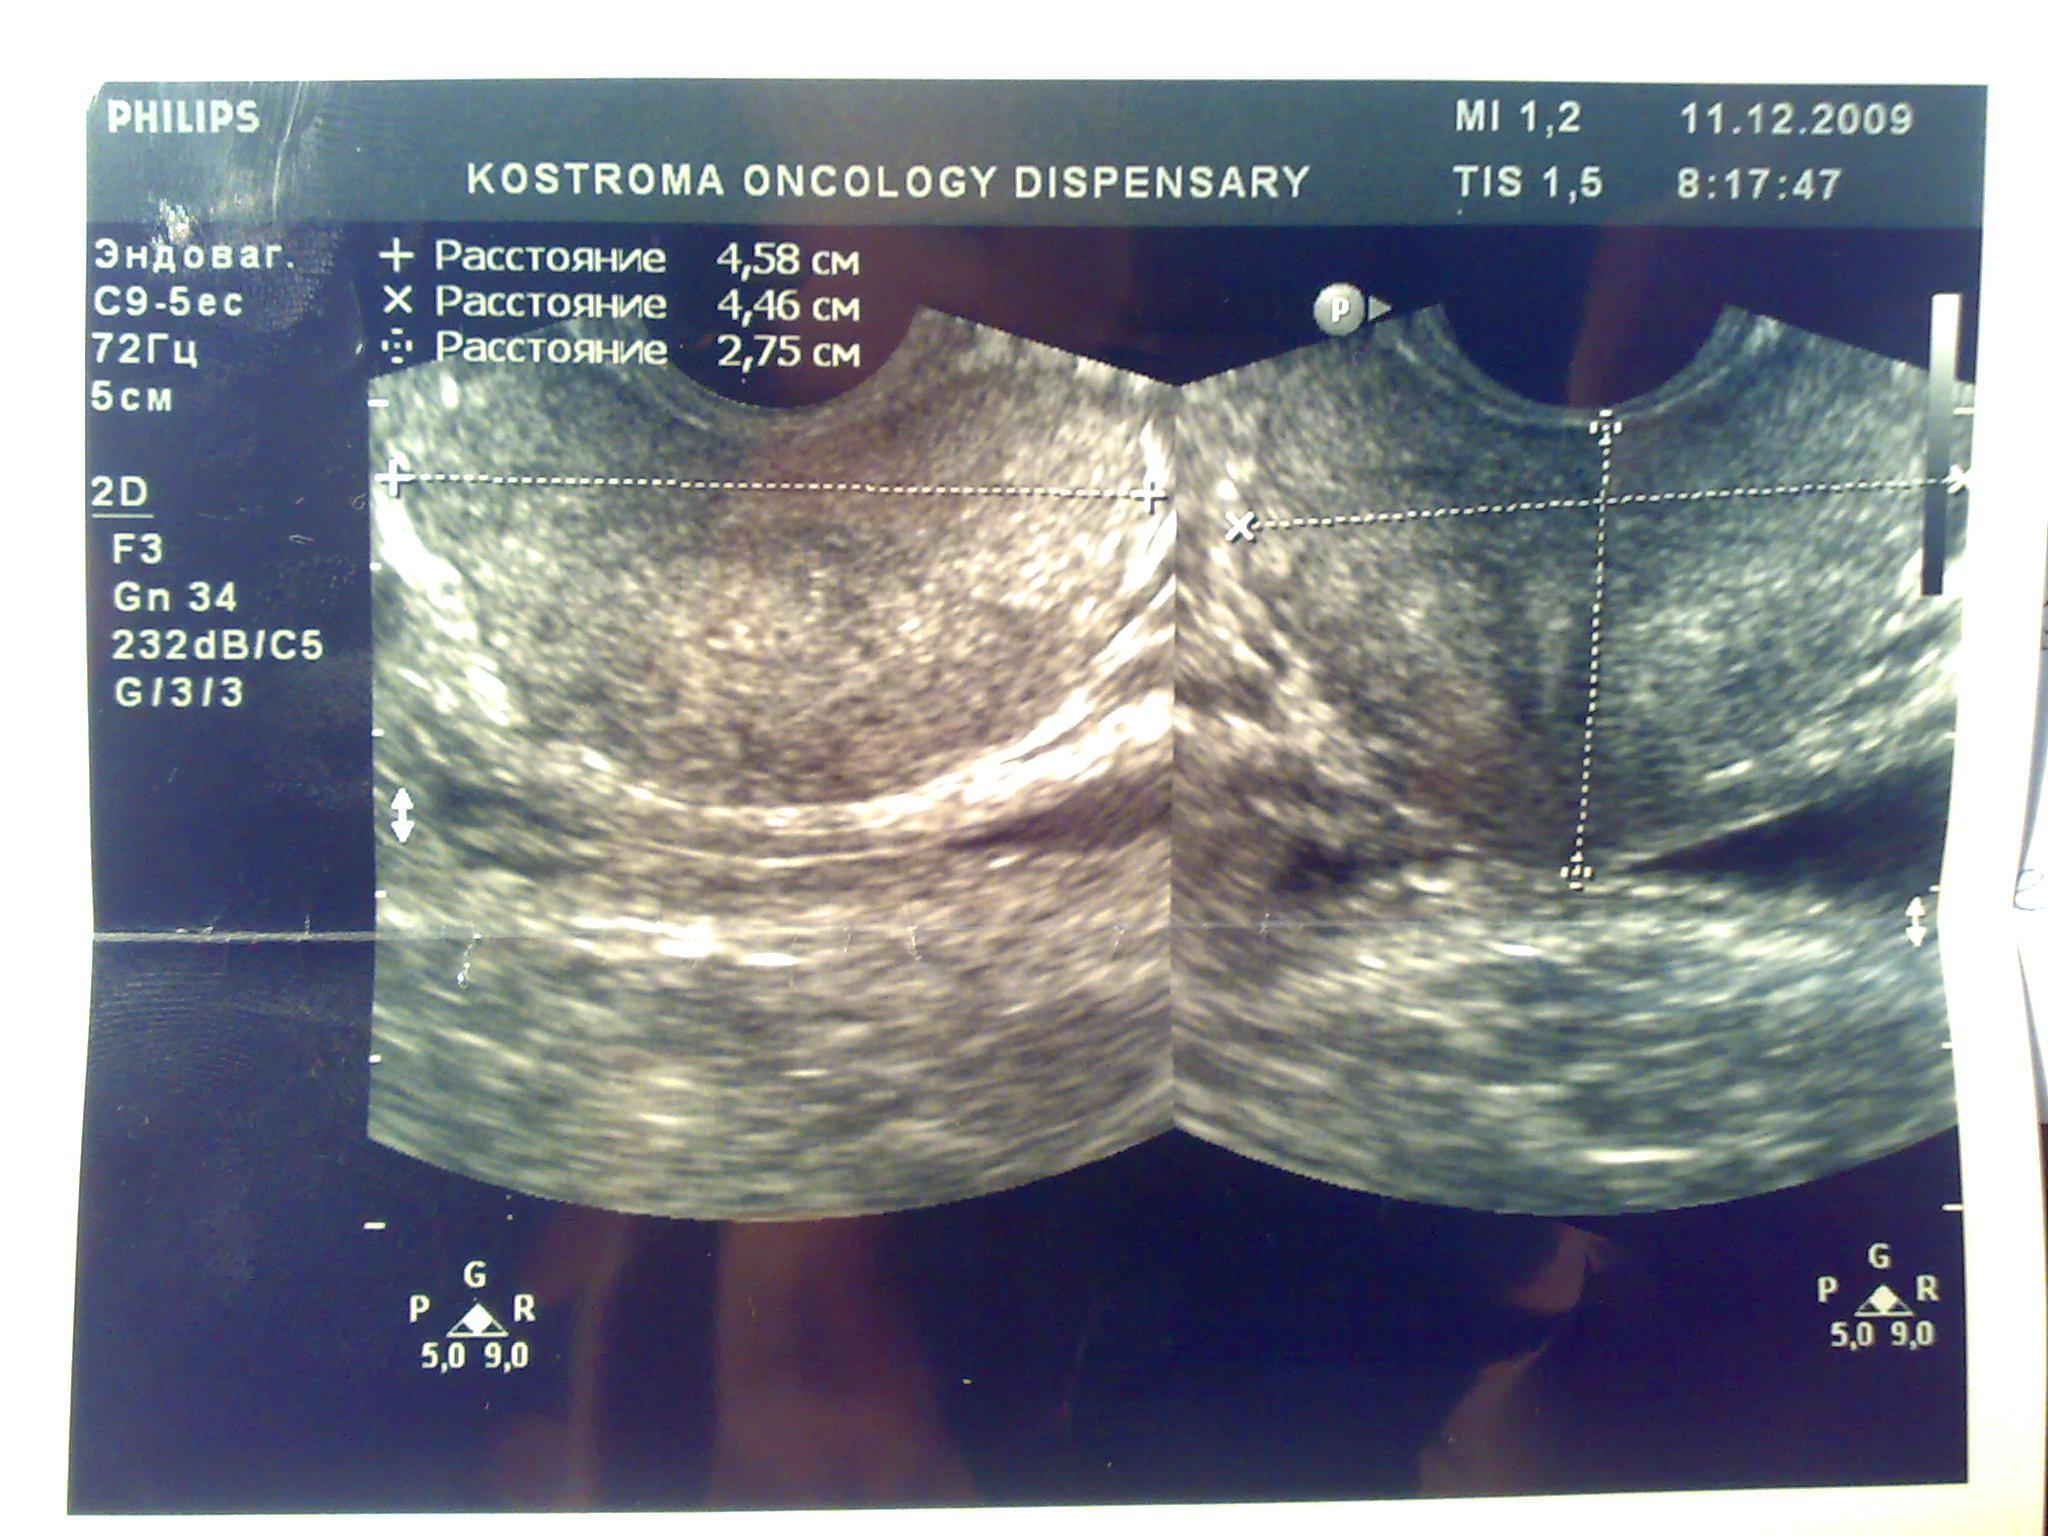

Доброго времени суток. В начале декабря сходил в банное заведение, употребил там пиво, вечером был сексуальный контакт с постоянной партнершей, на утро у обоих появилось жжение при мочеиспускании, у меня покраснение губок полового члена, умеренные выделения прозрачные, анализы крови и мочи в норме, ПЦР у обоих отрицательные. У девушки соэ 28, лейкоциты в моче выше 200, у меня все в норме, бак посев отделяемого из уретры выявил обильный рост Ешерихии коли, принимал внутремышечно Цефотаксим по 1г 2раза в день в течении 5 дней, во время лечения появилось жжение и дискомфорт в промежности. Трузи показало увеличение простаты, расширенные семенные пузырьки около 3 мм, кальцинатов и инфильтратов нет, в область мочевого пузыря не вдается, остаточное количество мочи около 10 мл, кол лейкоцитов в отделяемом из уретры 5-8 в поле зрения. Сейчас принимаю по назначению уролога Нолицин 400 мг по таблетке два раза в день, Палин 250 мг по 1 два раза и азитромицин 250 по одной раз в сутки, свечи на ночь Простатилен курс на 10 дней, уже прошло восемь массажей улучшение незначительное, симптомы в обшей картине сохраняются, железа со слов уролога стала более упругой и меньших размеров. У меня стала страдать эрекция, полной уже нет около 2 месяцев. После эякуляции хочется мочится, неприятные скребущиеся ощущения в промежности, сперма раньше выстреливала, а сейчас вытекает, выстреливает только первая порция, появились боли в мошонке слева, особенно после массажа, подскажите пожалуйста что делать, как лечится, какие еще анализы сдавать. Прикреплены снимки узи.Заранее благодарен.